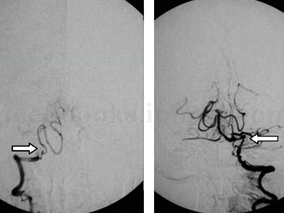

1小时条评论女,14岁,右利手。 主诉:突发右侧肢体偏瘫1年。 病史:1年前因突发右侧肢体活动障碍被外院诊断为脑梗死,在发病前没有外伤史、感染史(发热、上呼吸道感染、肠道感染),发病时无明显头痛。经保守治疗,保留右侧偏瘫后遗症至今。此后辗转于全国各大医院诊治查找...